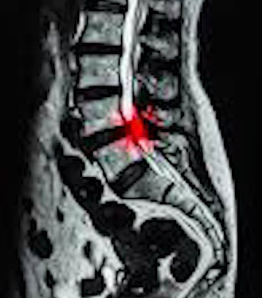

우리 몸은 여러 신경조직으로 구성이 되어 있고 신경 조직들은 뇌에서 시작해서 척추관을 지나 몸의 모든 부분으로 이어지게 되는데요. 척추협착증은 척추관이 다양한 원인에 의해서 좁아져 신경을 누르면서 통증을 동반한 유착과 염증을 일으키게 되는 증상입니다.

척추협착증 진단, CT와 MRI 촬영 등을 통해서 척추관 크기와 주변 관절과 인대, 추간판의 상태를 알아보고 종합적으로 진단을 하게 됩니다. 근전도 검사와 신경전도 검사도 함께 병행해서 하게 되겠습니다.